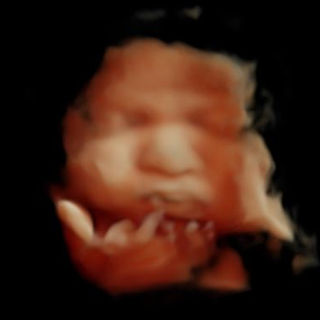

Gallery